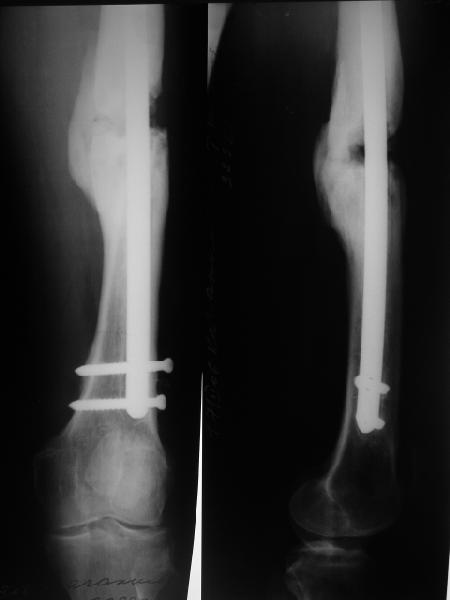

Тугой ложный сустав правого бедра в сочетании неправильно сросшимся переломом большеберцовой кости |

Уважаемые коллеги,В ортопедическое отделение обратился пациент: мужчина 47 лет, который в течение 4-х лет дваждыполучил травму костей, образующих правый коленный сустав. В 2002 v внутрисуставной оскольчатыйперелом проксимального метаэпифиза правой большеберцовой кости; в 2005 v внутрисуставнойоскольчатый перелом дистального метаэпифиза правой бедренной кости. В обоих случаях в разных лечебных учреждениях проводилось оперативное лечение переломов.При осмотре в отделении на основании результатов клинического осмотра и данных визуальныхметодов обследования поставлен диагноз:тугой ложный сустав дистальной трети правой бедренной кости, состояние после накостногоостеосинтеза перелома типа 33-В2.2 ; несросшийся перелом надколенника; неправильно сросшийсяперелом латерального мыщелка правой большеберцовой кости, состояние после металлоостеосинтезаперелома 41-В2.2; сочетанная осевая деформация правой ноги: варусная деформация правого бедра,вальгусная деформация правой голени; посттравматический артроз коленного сустава 4 ст по Kellgren-Lowrence; выраженное нарушение функции ходьбы и опоры. Внешний вид ноги больного, данные рентгенографического обследования и избирательно выделенные компьютерные томограммы приведены в приложении. В именах КТ использовано кодирование уровня по АО, т.е. _41, например, означает проксимальную треть голени.В отделении намечен v очень предварительно v следующий план лечения: 1. Иметь ввиду перспективу тотального эндопротезирования коленного сустава. 2. С учетом п.1 при проведении действий, направленных на устранение ложного сустава бедренной кости не использовать материалы, не подвергающиеся трансформации. 3. В ходе операции, направленной на устранение ложного сустава: А. удалить все металлоконструкции; Б. ревизовать зону пролежня под пластиной на бедре, при наличии признаков достаточной жизнеспособности кости выполнить остеопериостальную декортикацию, дрилинг ложа пластины; В. Удалить рубцовую ткань по плоскости ложного сустава, и в пространстве между костными форагментами, насечь обращенные друг к другу поверхности. Ввести штифт с блокированием (например Stryker с учетом особенностей расположения дистальных блокирующих винтов у этойконструкции). Осуществить остеосинтез с учтанением варусной деформации бедренной кости. Пространство в зоне ложного сустава и пустоты в метафизе бедренной кости заполнить резорбирующимся цементом на основе гидроксиапатита кальция. Для дистальной фиксации использовать винты с переменным шагом резьбы. Вариант:, винты вводить после заполнения метафиза цементом. Дополнительные виды создания межфрагментарной компрессии во встречно-боковом направлении обсуждаются. Г. Быть готовым к кровопотере. Д. Учесть высокий риск инфекции, тромбоэмболических осложнений. Е. Вопрос о внешней иммобилизации решить по результатам оценки стабильности остеосинтеза. Вариант - одноосевой стержневой аппарат для шунтирования гвоздя с модулем на голени и дистракцией коленного сустава в течение 3-5 недель. Просим вашей критики намеченного плана и конструктивных предложений. С уважением к сообществу, Ординатор В.С. Саплин